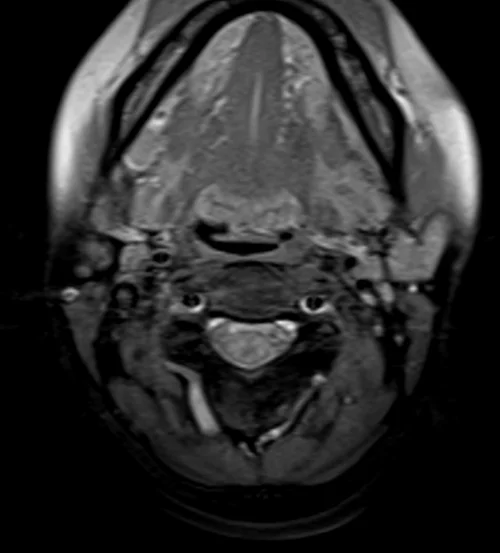

Neck MRA axial T1 fat sat images